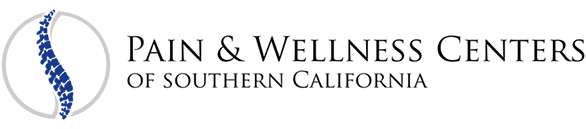

- Cervical and Lumbar Epidural Injections

- Rhizotomy